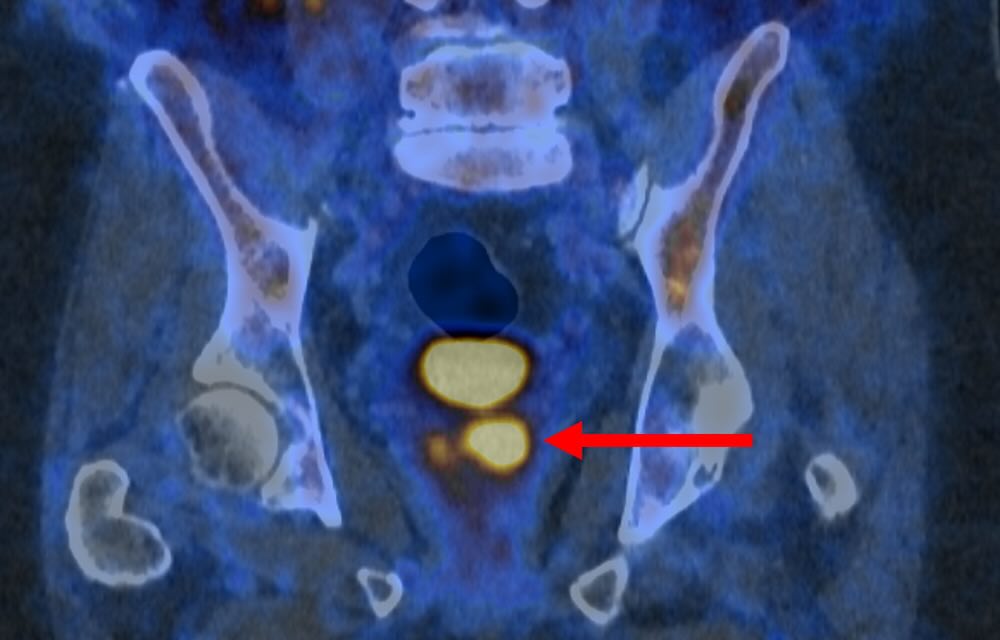

Using a specialized molecule that attaches to prostate cancer cells, this advanced imaging technique causes the cells to “glow,” presenting bright spots on the scan images. Australian scientists assert that this groundbreaking method could safely reduce the number of men requiring a biopsy by half after inconclusive MRI results.

The PSMA PET/CT scan is adept at identifying more aggressive prostate cancer cells, which could pose a threat and require treatment. Additionally, it plays a crucial role in minimizing over-diagnosis by differentiating between low-risk cancers that are unlikely to cause harm and those that need attention.

The Primary2 trial, which focused on men at higher risk for prostate cancer—such as those with a strong family history—randomly assigned participants to either receive a standard biopsy or the PSMA PET/CT scan. The findings revealed that the PSMA PET/CT scan could accurately identify individuals who did not have cancer or whose cancer was so low-risk or slow-growing that it would likely remain harmless.